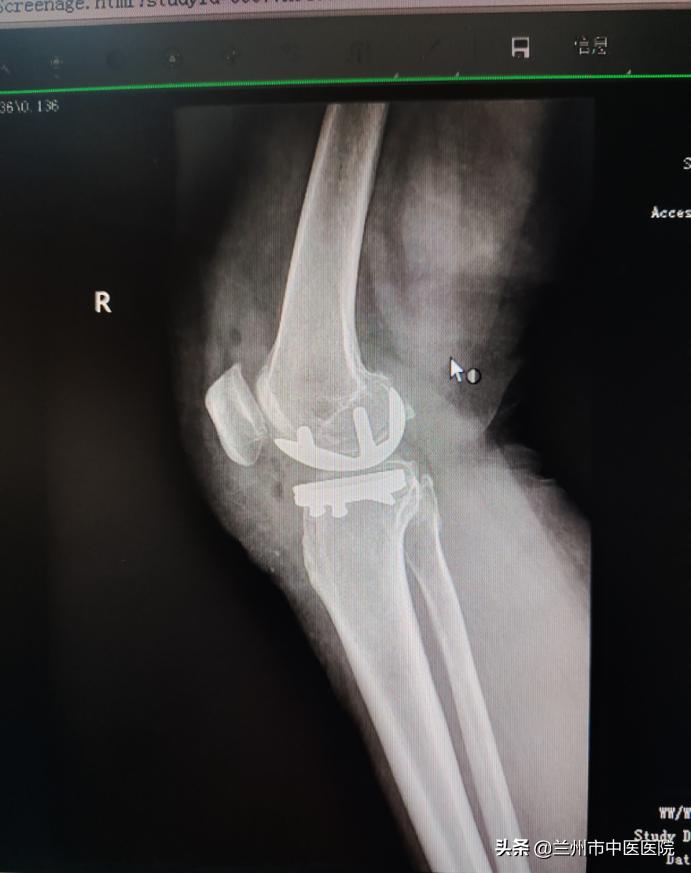

近日,兰州市中医医院骨科团队精诚合作,在麻醉科等相关科室的全力配合下,成功完成了单间室膝关节骨性关节炎、单髁置换术,手术顺利完成,病人术后恢复良好,家属满意。

膝关节的单髁置换手术,仅把膝关节的单侧髁部置换为表面假体。把膝关节由前正中线上等分,单侧髁部就是内侧或者是外侧的部分。简单来说,就是对一半膝关节进行置换,这一半膝关节主要构成是胫骨髁和股骨髁。当患者膝关节因骨性关节炎等发生了的严重病灶,但病变范围比较局限,该手术可以保留2/3正常的膝关节结构,让患者可以保留关节自然本体的感觉,恢复关节的活动,还可以延缓患者做全膝关节置换的时间。

单髁置换术具有手术创伤小、术后恢复快、病人疼痛轻、失血少、术后本体感觉好、花费少等特点。用于膝关节早期病变,可明显改善病人生活质量,延缓病人的全膝置换时间,对很多患者来说可以免除全膝关节置换。

单髁置换术特点:相对于全膝关节置换术,单髁置换术具有以下特点:创伤小。手术切口大约只有传统全膝关节置换手术的一半,切除置换的骨与软骨组织不到传统手术的三分之一;疼痛轻。术后疼痛较轻,在规范的镇痛方案辅助下,多数患者几乎感觉不到疼痛;恢复快。大多数患者术后当天即可下床活动并完成日常生活,一个月以内基本恢复正常状态;更接近正常的生理活动。由于保留了膝关节的正常结构,接受这类保膝手术的患者术后膝关节能够完成膝关节旋转、极度屈曲、深蹲等动作。